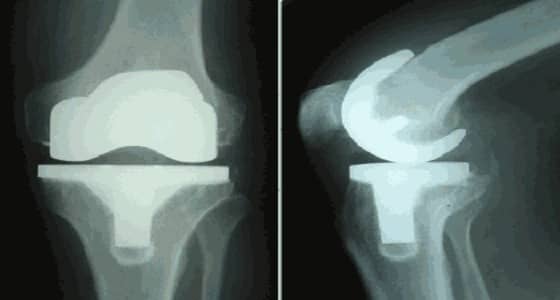

نجح الأطباء في مكة المكرمة ، في إجراء عملية جراحية تضمنت تغيير ركبتي مريض كان يعاني من خشونة وتقوس بدرجة 40 لمدة عامين.

وأكد الدكتور عبدالظاهر الساعاتي الذي أجرى العملية أن الصعوبة كانت تكمن في أنها للركبتين معًا، والمريض كان يعاني من تآكل في عظام الركبتين بسبب الخشونة.